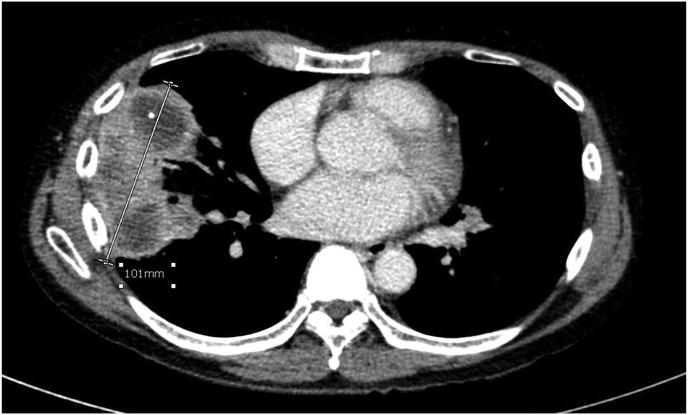

Granulomatous polyangiitis (GPA) is a multiple systemic necrotizing vasculitis. Diagnosis of pulmonary nodules in GPA is still challenging in clinical practice, however, other extrapulmonary manifestations, serology, and histopathology may help the diagnosis of GPA. This case series was of limed GPA with one of the largest pulmonary nodules which had a poor treatment response in contrast with previous literature.

肉芽肿性多血管炎(GPA)是一种多系统坏死性血管炎。在临床实践中,GPA中肺结节的诊断仍然具有挑战性,然而,其他肺外表现、血清学和组织病理学可能有助于GPA的诊断。本病例系列为局限性GPA,其中一个肺结节最大,与既往文献相比,治疗反应较差。